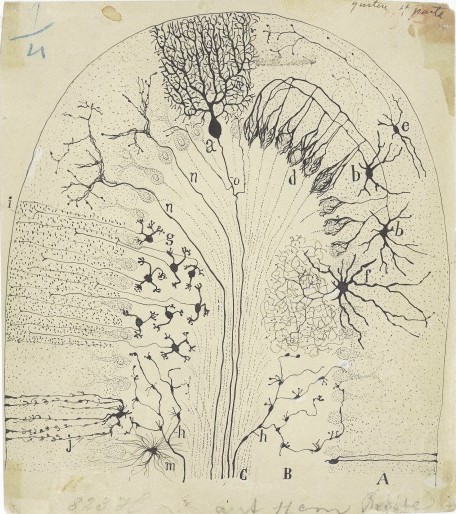

As we cover each relevant section, the exhibition provides an overview of the disputed territories of the brain, and thence to epic moments in the history of neuroscience. We encounter the work of the father of modern neuroscience, the Spanish Nobel Prize-winner Santiago Ramón y Cajal, whose pioneering research at the turn of the 20th century gave us an understanding of the microscopic structure of the brain. Having displayed an early talent for drawing and painting, Cajal had longed to train as an artist, but his father had insisted he follow the family tradition into medicine.

As we cover each relevant section, the exhibition provides an overview of the disputed territories of the brain, and thence to epic moments in the history of neuroscience. We encounter the work of the father of modern neuroscience, the Spanish Nobel Prize-winner Santiago Ramón y Cajal, whose pioneering research at the turn of the 20th century gave us an understanding of the microscopic structure of the brain. Having displayed an early talent for drawing and painting, Cajal had longed to train as an artist, but his father had insisted he follow the family tradition into medicine.

Cajal’s intricate drawings of the brain’s cellular structure show the hand of an impressive draughtsman – he made thousands of drawings on any scrap of paper he could find, accurately describing the brain’s complex circuitry (see picture above, drawing 1894; bottom: box model of the brain, mid 20th century, University of Aberdeen). In these beautiful, sinuous depictions, which suggest a beguiling “garden of neurology”, we find tree-like branches and roots and tissue strata, and marvel at such replications in nature.